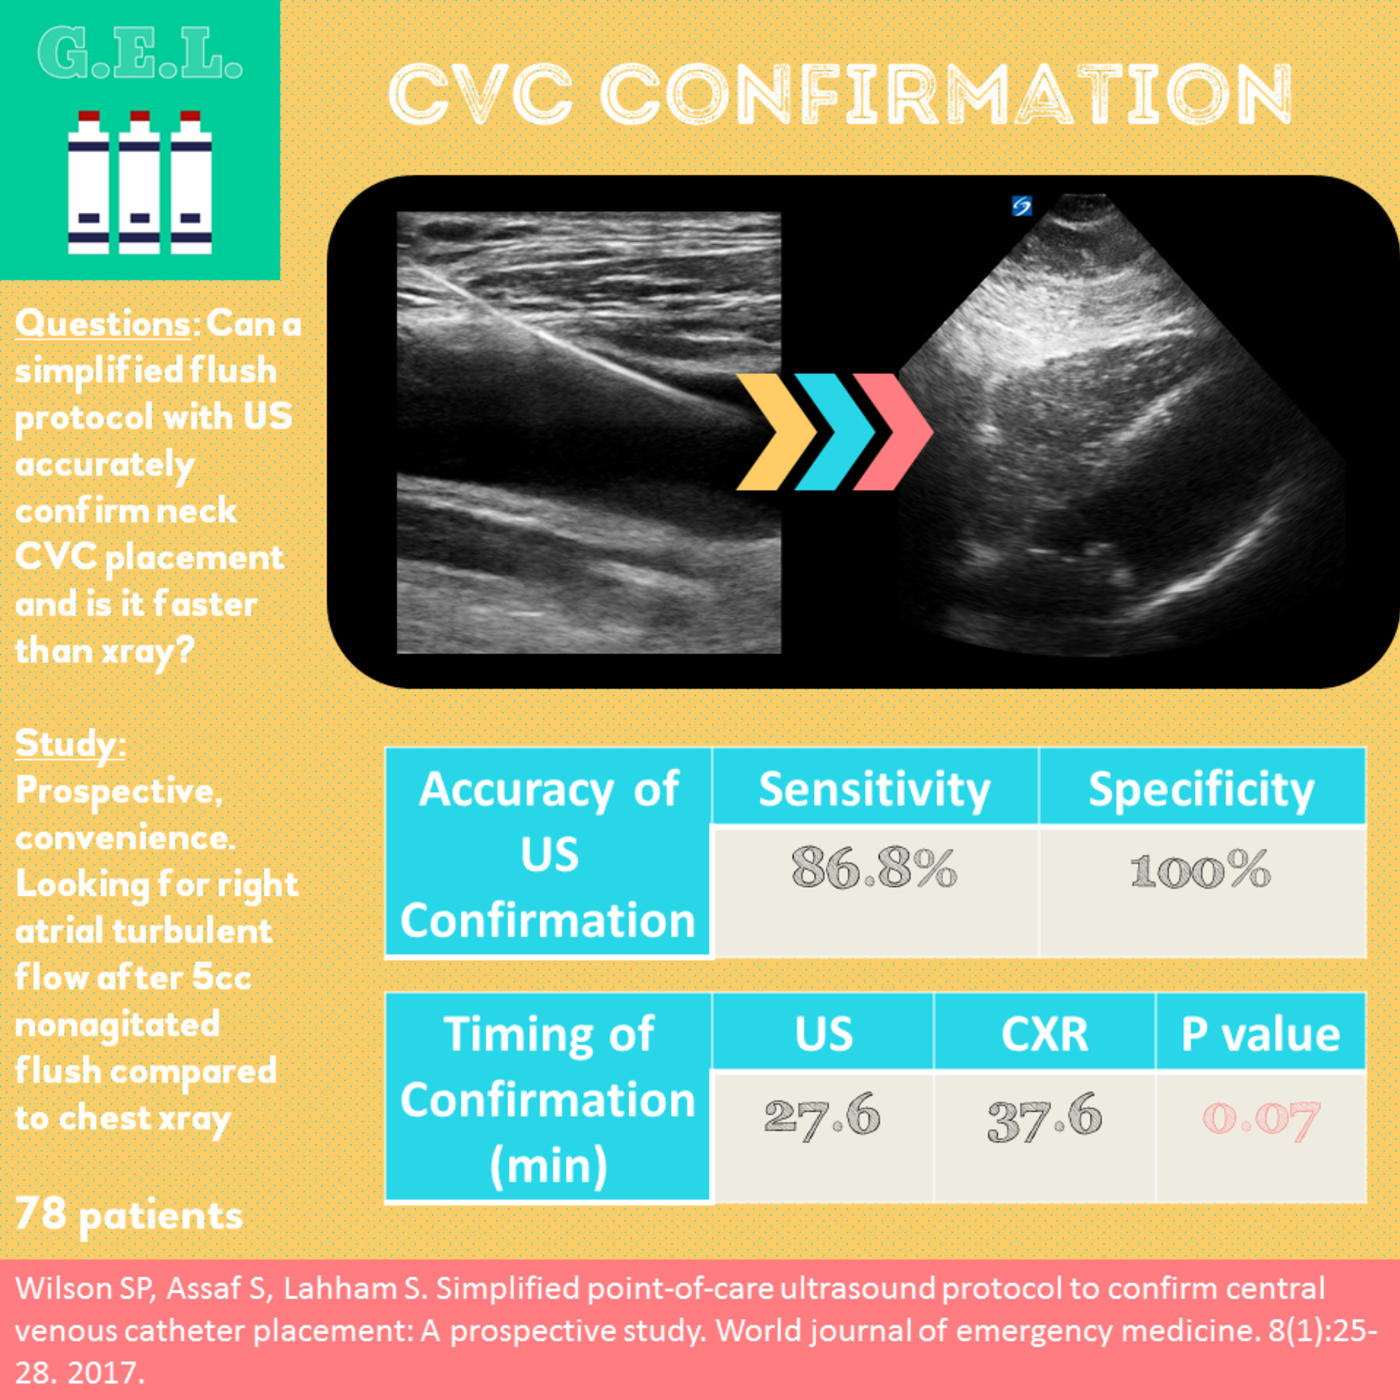

A central venous catheter was placed in the right internal jugular under ultrasound guidance and subxiphoid view was obtained. Saline was rapidly flushed through the brown port and turbulent saline can be seen traveling through the right side of the heart. - Dr. Matthew Riscinti and Dr. Isaac Gordon - Kings County Emergency Medicine